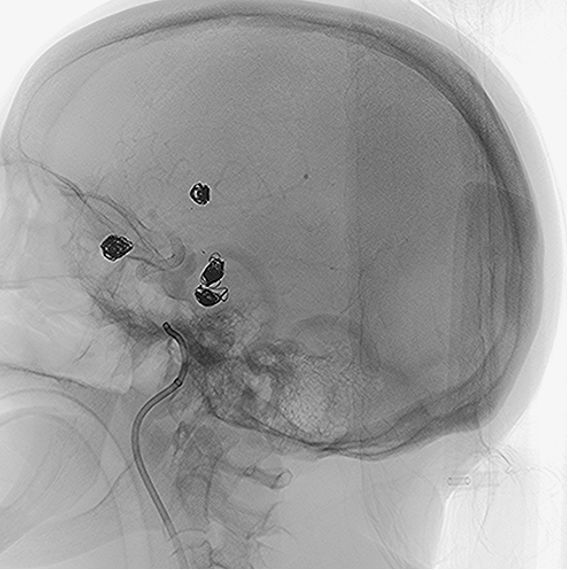

• A 5x20mm NUVA flow diverter, designed by TJWY, was deployed to treat the aneurysm in the posterior communicating artery with precision, achieving immediate blood flow stagnation.

• The neck of another aneurysm in the pericallosal artery was protected with a 10mm PCONUS intrasaccular device, and successfully embolized with 3 coils.

• The NUVA flow diverter demonstrated excellent wall apposition without complications.

• Post-surgery, branch vessels were fully preserved, and the patient’s recovery was smooth with no adverse events.